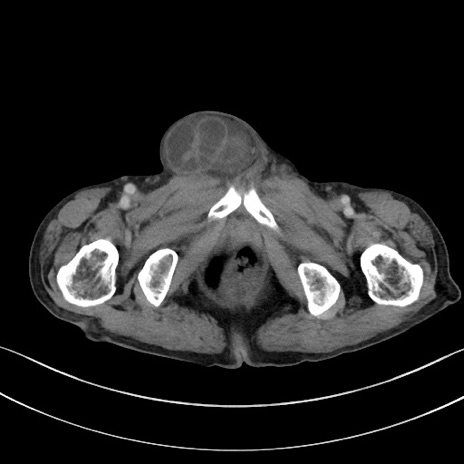

症例3(横断像)

【症例】 70歳代男性

【主訴】右鼠径部腫瘤、疼痛

【現病歴】本日朝より上記主訴あり、受診。

【既往歴】膀胱癌にて膀胱全摘、両側尿管皮膚瘻

【データ】WBC 5600、CRP 0.56